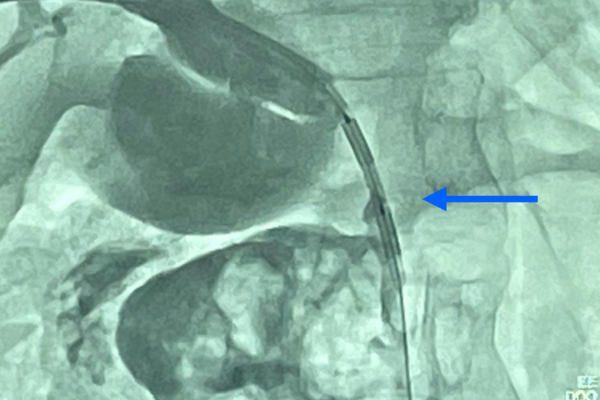

Equipes da Radiologia Intervencionista, da Cirurgia Geral e da Oncologia participaram do procedimento

Recife (PE) – Uma paciente idosa, de 68 anos, acompanhada pela Área Assistencial de Cirurgia Geral do Hospital das Clínicas da UFPE passou por um procedimento inovador no Sistema Único de Saúde (SUS) para tratamento de um câncer hepatobiliar, por meio da ablação (uma espécie de “queimagem”) por radiofrequência percutânea. Os resultados preliminares indicam a melhora da paciente, sinalizando a possibilidade de um tratamento eficaz para esse tipo de câncer e pouco invasivo. O HC é uma unidade vinculada à Empresa Brasileira de Serviços Hospitalares (Ebserh).

“Uma radiografia de controle realizada 15 dias após a ablação revelou uma desobstrução parcial do canal biliar, demonstrado que esse tratamento poderá se tornar uma alternativa promissora para esse tipo de câncer irressecável (tumor que não pode ser removido cirurgicamente)”, comenta o coordenador da Área Assistencial de Radiologia Intervencionista do HC, Laécio Leitão, um dos responsáveis pelo procedimento.

A alternativa para a melhora da paciente foi o uso de uma nova tecnologia chamada radiofrequência endobiliar, que permite a destruição de células cancerígenas, por meio da elevação da temperatura local. “Esse dispositivo está montado na extremidade de um cateter, que é introduzido através do fígado por um corte de 3 milímetros e guiado por um aparelho de raios-x chamado angiógrafo”, relata Laécio Leitão.

Leitão explica ainda que, num primeiro momento, houve a drenagem do canal biliar obstruído pelo tumor, o que permitiu a melhora da icterícia e da infecção na paciente. Cinco dias depois, foi realizada a ablação (“queimagem”) do tumor por radiofrequência.